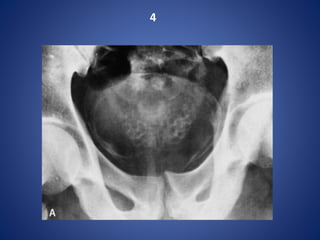

SCHISTOSOMIASIS OF UB

5